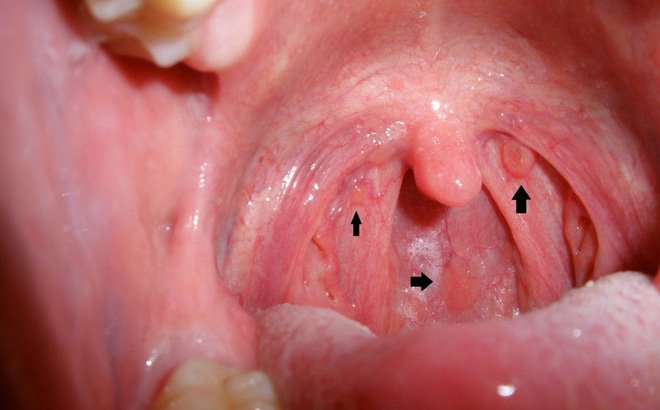

Ung thư vòm họng là ung thư xảy ra ở môi (thường là môi dưới), trong miệng, cuống họng, hạch amidan hay các tuyến nước bọt. Thường gặp ở nam nhiều hơn nữ, và thường tấn công nhiều nhất vào những người trên 40 tuổi. Hút thuốc cùng với uống rượu nhiều là một yếu tố nguy cơ chủ yếu.

Các Triệu Chứng của Ung Thư Vòm Họng

Các Triệu Chứng của Ung Thư Vòm Họng

Bạn sẽ không thể tự phát hiện được các triệu chứng sớm của ung thư vòm họng, cho nên đi khám bệnh thường xuyên với cả nha sĩ và bác sĩ là điều rất quan trọng. Nha sĩ là người được đào tạo để phát hiện các dấu hiệu sớm của ung thư miệng. Tuy vậy, cùng với việc đi khám định kỳ, bạn cũng nên đến gặp nha sĩ khi có bất kỳ dấu hiệu nào sau:

– Cảm giác đau ở môi, nướu, hoặc vùng trong miệng dễ chảy máu và vết thương không lành.

– Khối u hay sự dày lên ở mặt trong má mà bạn cảm nhận được bằng lưỡi.

– Mất cảm giác hay tê ở bất kỳ vị trí nào trong miệng.

– Những mảng đỏ hoặc trắng trên nướu, lưỡi hoặc bên trong miệng.

– Khó nhai và nuốt thức ăn.

– Đau hoặc nhức không rõ nguyên nhân, hoặc cảm giác có dị vật trong họng.

– Sưng hàm dẫn đến hàm giả bị lỏng.

– Giọng nói thay đổi.